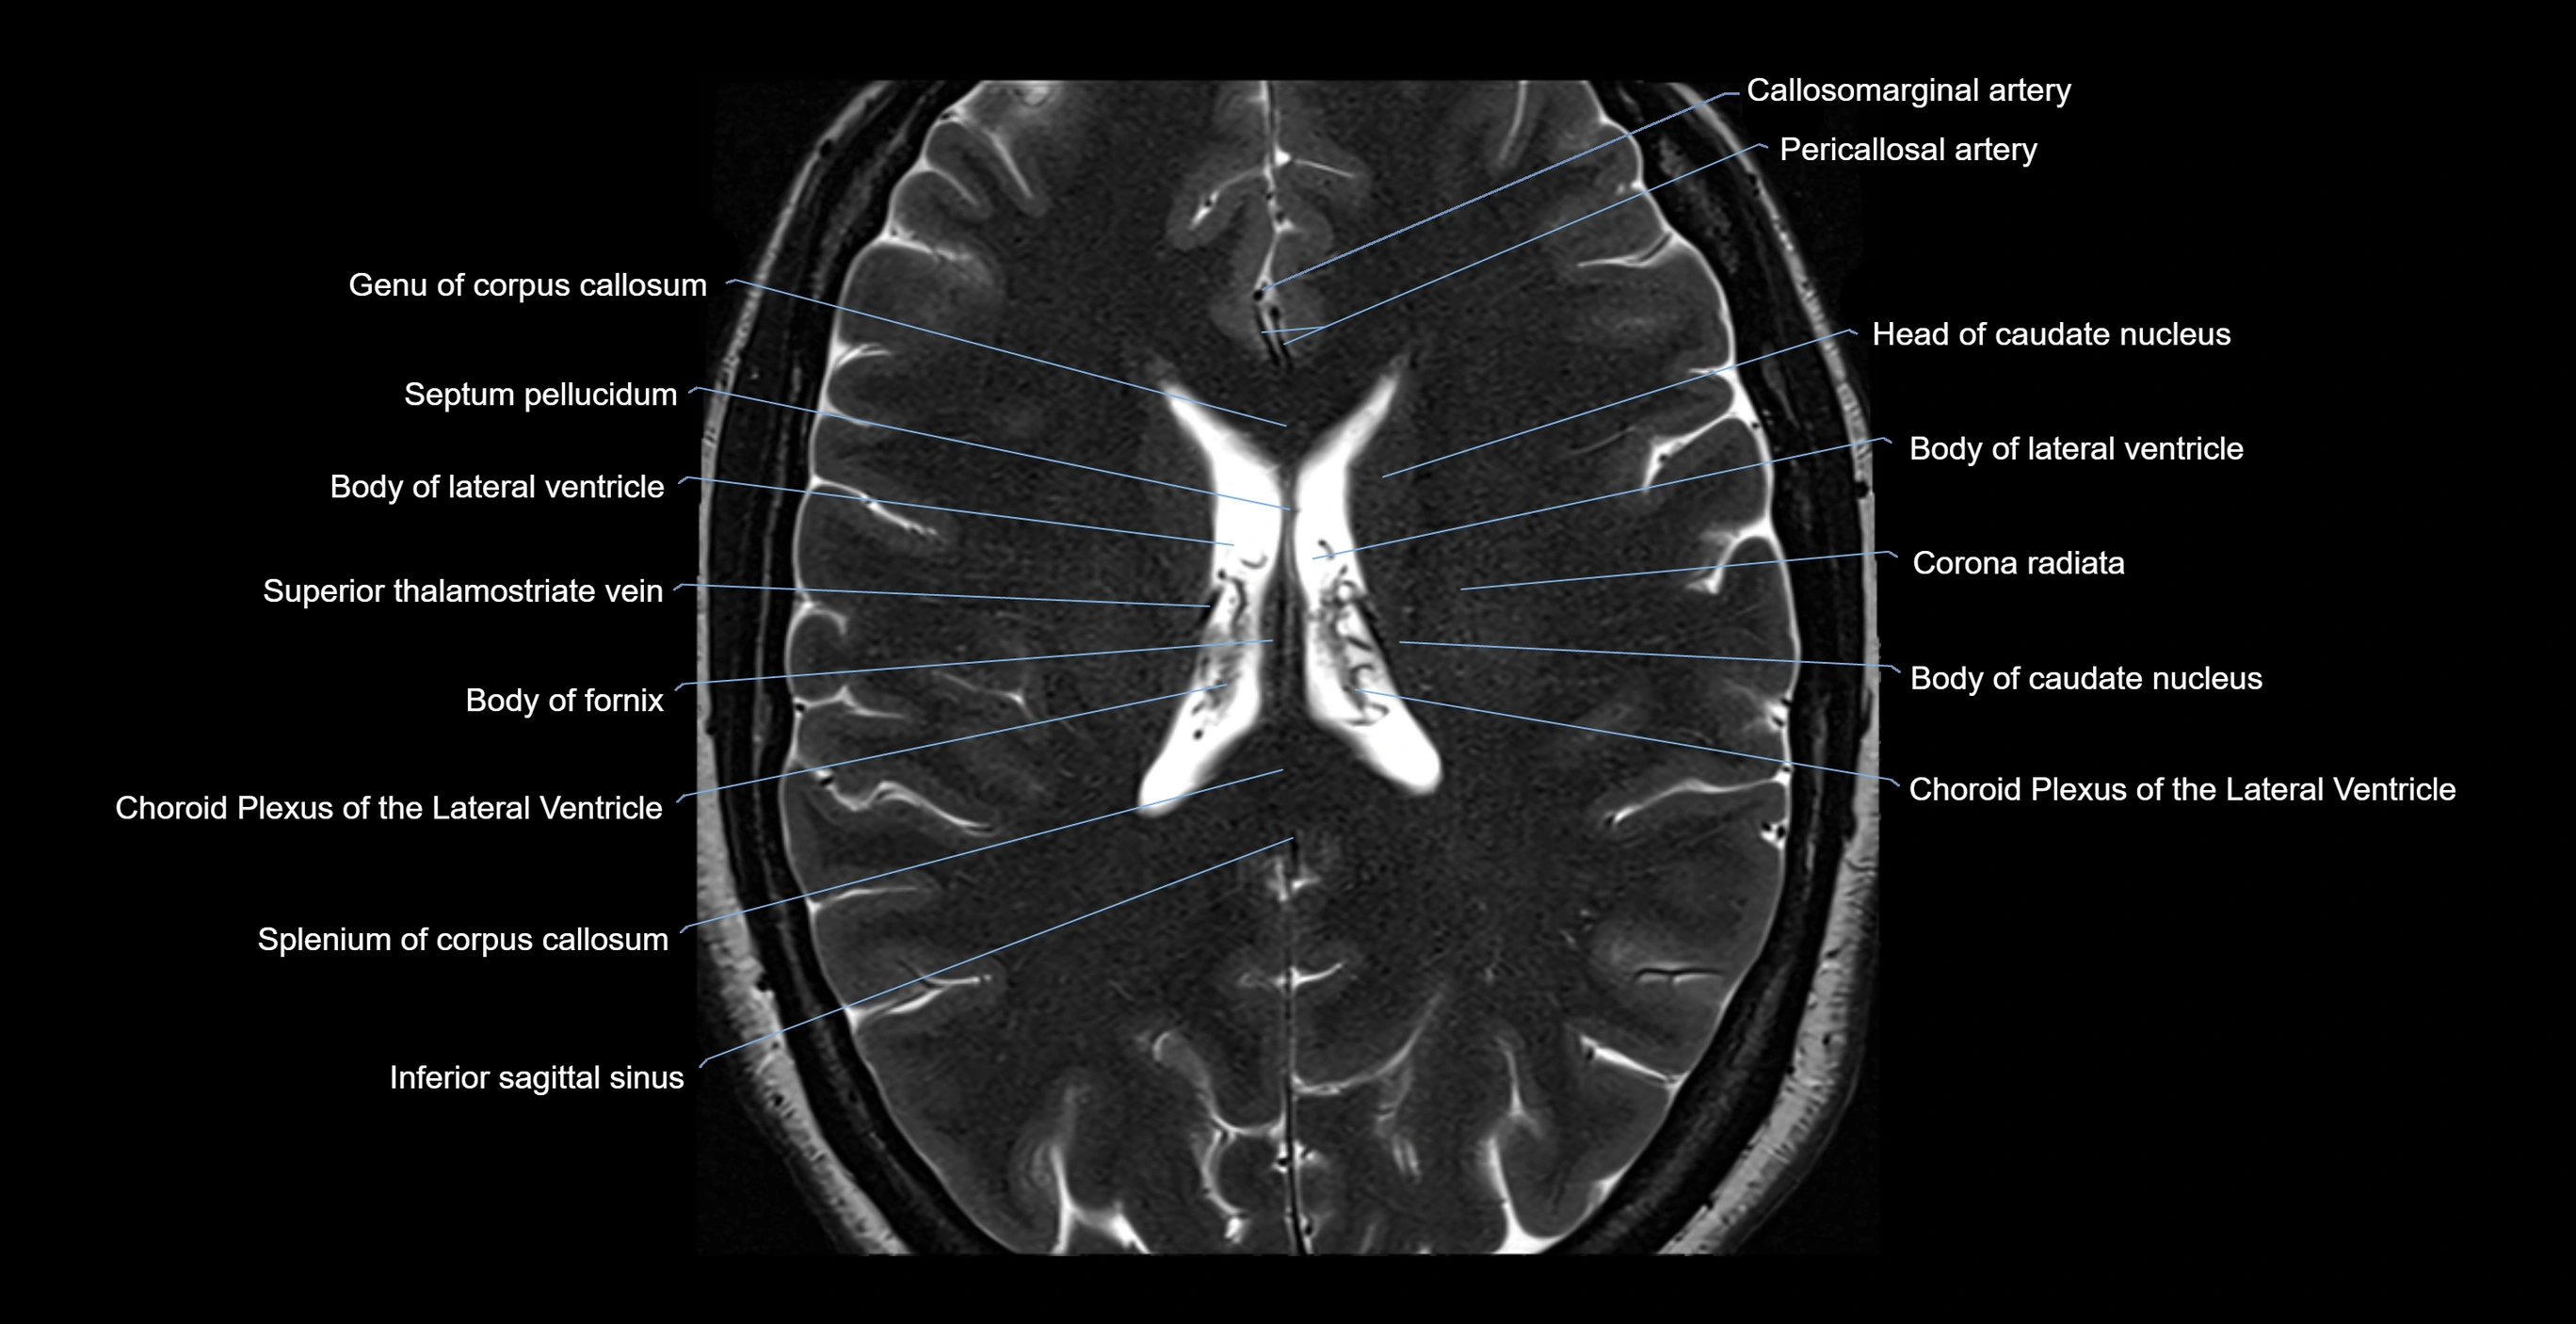

MRI images